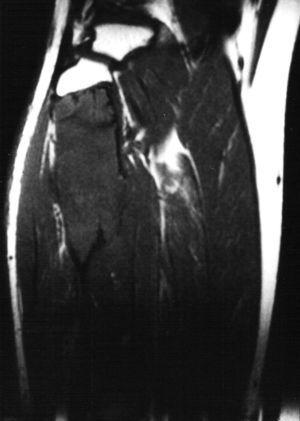

Paciente varón de 15 años, que fue remitido a consultas de traumatología por genu valgo. No tenía antecedentes de interés, salvo crisis asmáticas en la infancia, y la presencia de una lesión lítica ya conocida en el peroné, que sugería el diagnóstico diferencial de displasia fibrosa o quiste óseo aneurismático como primeras posibilidades. La lesión parecía haber crecido respecto a estudios previos. En la radiografía simple (fig. 3), se identificaba una gran lesión lítica expansiva que afectaba predominantemente a la metáfisis proximal del peroné derecho, extendiéndose caudalmente a la diáfisis, y limitada superiormente por la placa de crecimiento. No tenía matriz ósea interna y la zona de transición, al menos en la zona inferior, era estrecha. En el interior presentaba un patrón de múltiples septos con cierto adelgazamiento endostal. En la TC (fig. 4) la cortical estaba muy adelgazada, con focos de discontinuidad sin identificar masa de partes blandas, y presentaba finos septos internos. Se realizó un estudio mediante RM con un equipo de 1,5T (Gyroscan Philips Intera). En la RM el tamaño aproximado de la lesión era de 8,5 x 3,3 x 3 cm (craneocaudal x anteroposterior x lateromedial). La lesión insuflaba el peroné sin visualizar masa de partes blandas. En la secuencia T1-ES (TR/TE 460/15) se comportaba hipointensa de forma homogénea (fig. 5). En la secuencia STIR (1688/15) (fig. 6) parecía tener dos componentes, con diferentes intensidades de señal. El superior hipointenso y el inferior levemente hiperintenso. En la secuencia dinámica T1 (TR/ TE 460/15) tras gadolinio itravenoso (figs. 7 y 8) presentaba un leve realce periférico del componente superior en fase tardía con prácticamente nulo realce en fase precoz y, sin embargo, un intenso realce del componente inferior en fase precoz, seis segundos después de que el contraste se identificase en el interior de los vasos arteriales, con realce persistente en fase tardía (fig. 9). Se realizó una gammagrafía ósea de cuerpo completo en proyecciones anterior y posterior en tres fases. En la fase vascular se observaba un incremento en la llegada del radiotrazador del pool sanguíneo a la región proximal del peroné derecho. La imagen tardía mostraba una hipercaptación en el extremo proximal de dicho hueso. Descartaba la posibilidad de quiste óseo, que no suelen mostrar captación en la gammagrafía y aconsejaban descartar otro tipo de tumoración ósea. No se visualizaron otras lesiones a distancia. En estos momentos el diagnóstico diferencial propuesto fue de fibroma condromixoide, fibroma desmoplásico y quiste óseo aneurismático, a pesar de la ausencia de niveles líquido-líquido. A continuación se realizó una biopsia abierta, con diagnóstico de fibroma desmoplásico. En el estudio macroscópico se identificaban varios fragmentos blanquecinos de consistencia ósea. En el estudio microscópico, se identificó una proliferación de células elongadas, separadas de abundantes fibras de colágeno. La densidad celular era muy variable en función del campo estudiado, lo mismo que la disposición de las fibras de colágeno, bien onduladas o con gran laxitud. Las células tenían núcleos ovoideos, sin aparentes nucleolos y sin figuras mitóticas. Algunos de los remanentes óseos atrapados en la muestra tenían actividad osteoclástica, sin ver en ningún momento atipias.

Fig. 5.--Secuencia coronal T1-ES. La lesión aparece homogéneamente hipointensa, de comportamiento expansivo, limitada superiormente por la phisis.

Fig. 6.--Secuencia STIR coronal. Se diferencian los dos componentes. El superior hipointenso con una halo de hiperseñal y el inferior hiperintenso sin asociarse a masa de partes blandas.